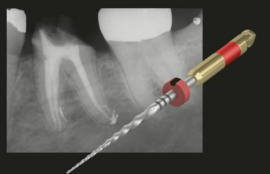

Spezielle extrem biegefreudige und dabei bruchfeste Instrumente ermöglichen eine ideale Erweiterung und Ausformung auch stark gekrümmter Wurzelkanäle. Eine echte Revolution stellt die sog. reziprok-arbeitende maschinelle Aufbereitung dar (stetiger Wechsel von Vor- und Rückwärtsbewegungen), um ein Verklemmen des rotierenden Instrumentes im Wurzelkanal zu verhindern.